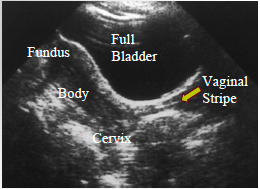

identify the bladder, fundus, body cervix and vaginal stripe

Uterus from cervix to fundus, showing vaginal stripe & endometrial stripe